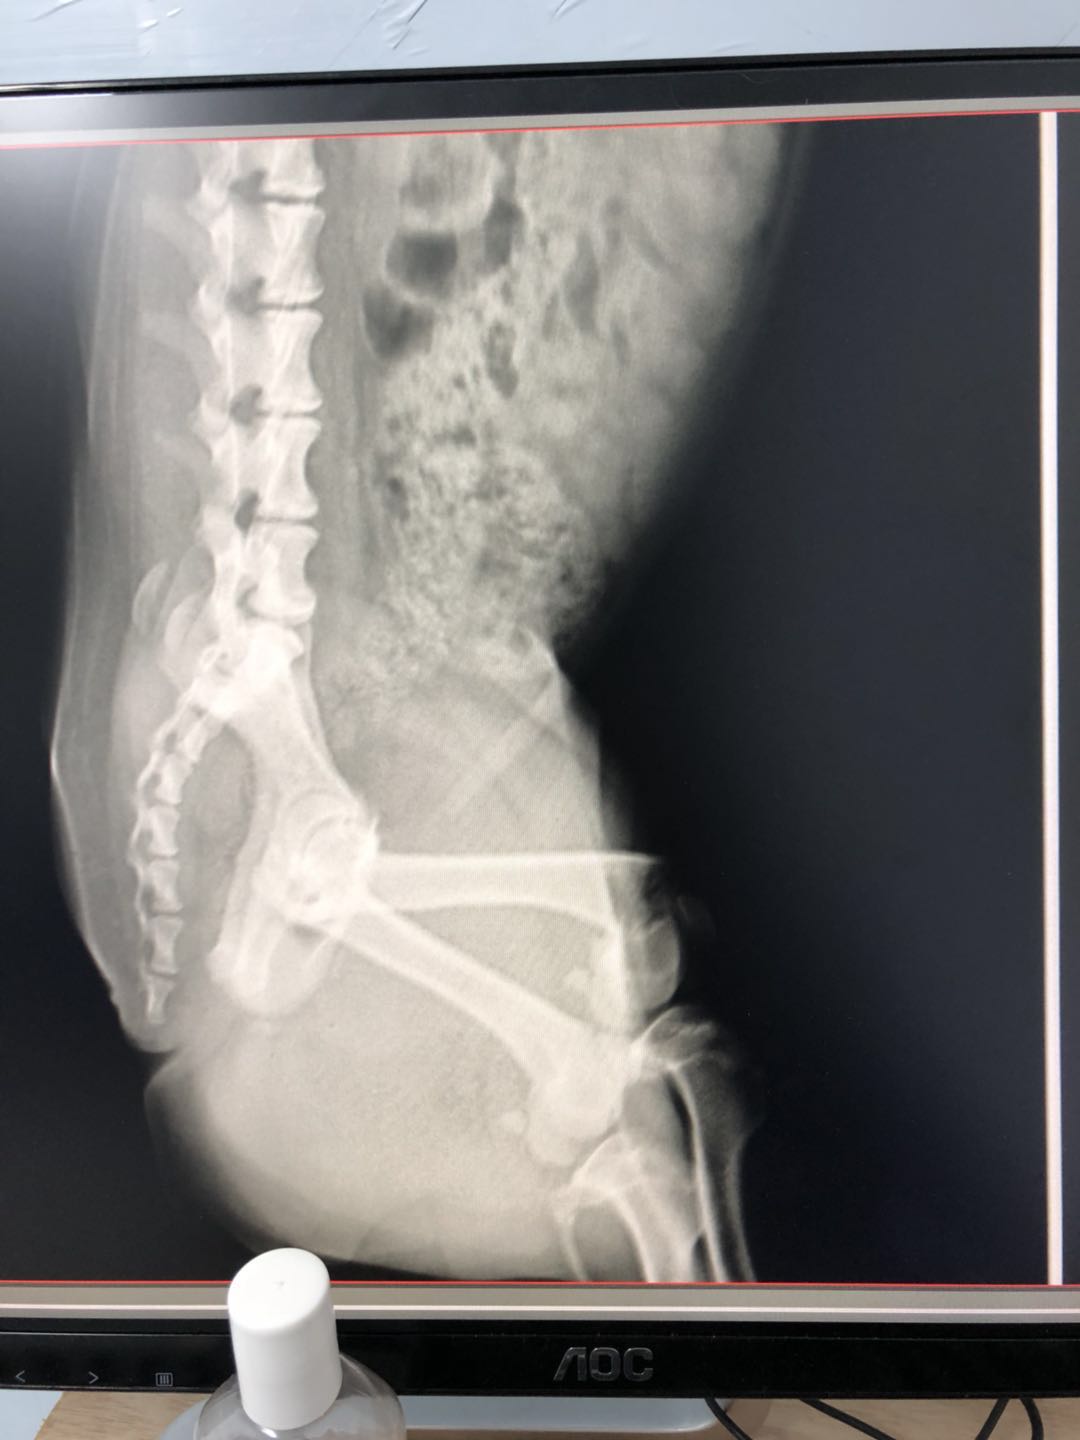

骨折完美复位的小柯基,医生们技术真到位